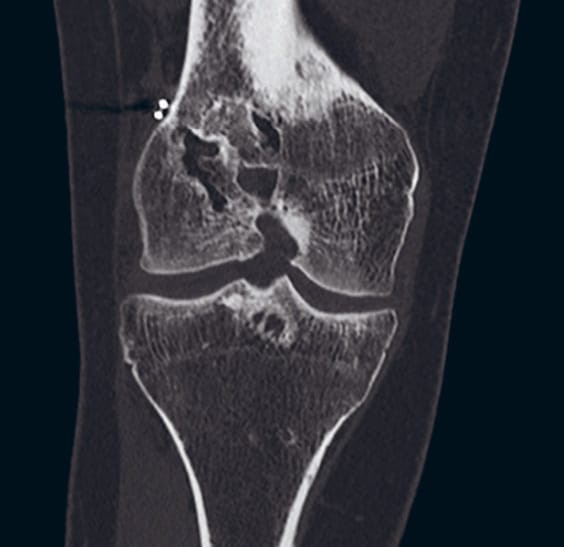

Six months after the tibial tunnel bone grafting, there was still a very large tibial defect. Rather than performing a repeat tibia bone graft, we elected to use a laterally-based tibial tunnel. The tunnel was created just adjacent to the tibial tubercle to go on the lateral side and was drilled through entirely virgin bone.

On the femoral side, there was no significant bone defect, however the bone was quite soft and we elected to use suspensory fixation, tying over a button. We used an anteromedial inferior portal to create our femoral socket. We reamed that by hand on the femoral side to avoid posterior cortex blowout.

The lateral femoral cortex was exposed for the ITB extra-articular tenodesis. We left harvested the central 1cm of the ITB and left it attached distally and tunneled it under the proximal FCL just distal to the lateral epicondyle of the femur. We then created a socket in the lateral femur in a position that was isometric from 0 to 30° of flexion. After docking the ITB in the socket, we pulled our sutures out medially and used an interference screw to fix the ITB on the lateral side.

The patient was treated with full motion and weight bearing as tolerated. She regained full motion in both knees by two months postoperatively and her instability was eliminated as recently as her two-year follow up.